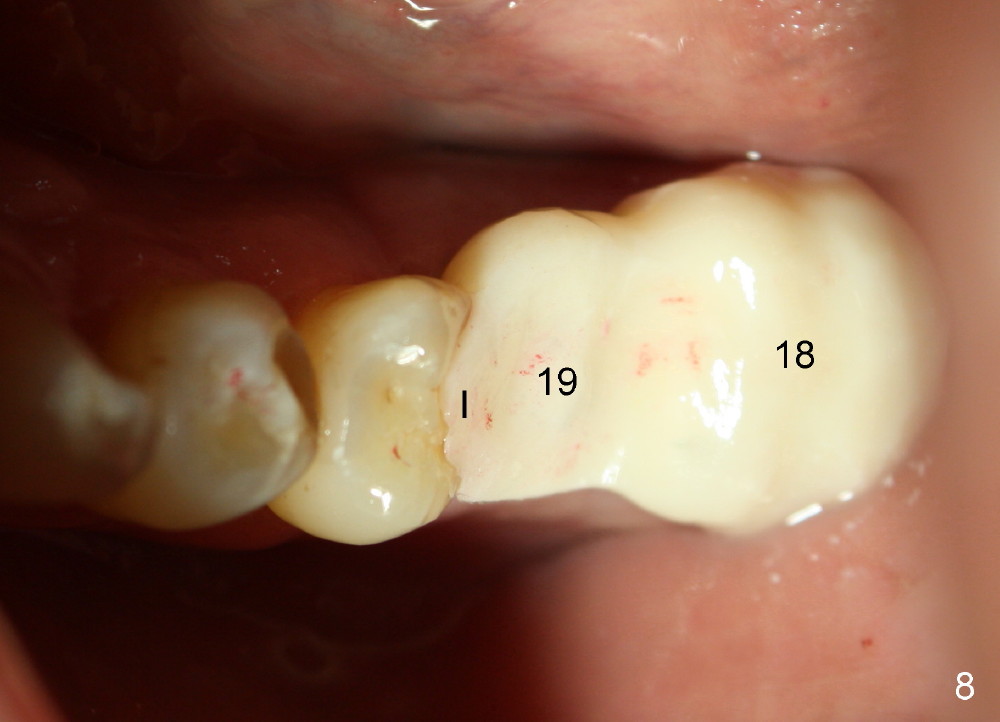

One week postop, the perio dressing stays in place (Fig.7). Then the patient is out of town. When he returns 3 weeks postop, the provisional bridge is fabricated as mentioned above (Fig.8). The provisional breaks down soon and are repaired multiple times, since there are multiple missing teeth. The patient is not eager to have ideal occlusion and wants restoration quick. We may try ortho in the upper right area.